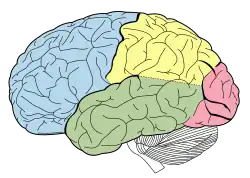

Lobes of the human brain (the occipital lobe is shown in red) | |

The occipital lobe is one of the four major lobes of the cerebral cortex in the brain of mammals. The name derives from its position at the back of the head, from the Latin ob, 'behind', and caput, 'head'.

The two occipital lobes are the smallest of four paired lobes in the human brain. Located in the rearmost portion of the skull, the occipital lobes are part of the posterior cerebrum. The lobes of the brain are named from the overlying bone and the occipital bone overlies the occipital lobes.

Drawing to illustrate the relations of the brain to the skull. Occipital lobe in blue

Occipital lobe in blue Occipital lobe